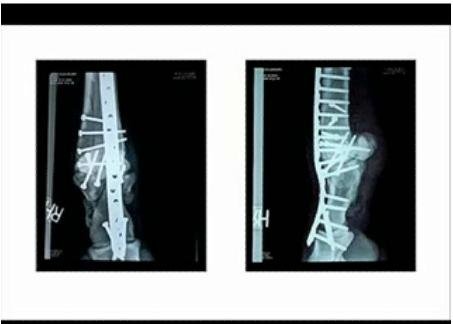

Překážkou v postupu, co jinak vypadalo jako nevšední zotavování z mnohonásobné fraktury se na začátku ledna stala Barbarova levá zadní noha. Po první operaci, kdy byly Barbarovy zlomené kosti sešroubovány, přílišná zátěž druhé nohy a minimální pohyb vedly k akutnímu zánětu škáry levého zadního kopyta, a k odnětí 80% kopytního pouzdra (červenec 2006). Ačkoli na vnější straně kopytní pouzdro narostlo do své takřka původní délky, vnitřní stěna rostla o poznání pomaleji (v lednu 2007 pouhých 10%).

V průběhu ledna dali veterináři Barbarovi sádrový obvaz, aby podpořili správnou polohu kopytní kosti. Viditelné nepohodlí koně a reinspekce kopyta vedly Richardsona k tomu, aby odňali další část nově separované stěny na vnitřní straně levého zadního kopyta (9. ledna večer), a opět přeťali šlachu hlubokého ohýbače prstu, čímž chtěli snížit jeho tah na kopytní kost. Šlachu přeťali už podruhé, protože od prvního zákroku se zahojila a její tah na kopytní kost vzrostl a způsoboval její rotaci. Rovněž zasádrovali dolní část pravé zadní nohy, aby dodali další potřebnou podporu.

Během tohoto období, kdy kůň trpěl více než obvykle, začal Barbaro více zatěžovat pravé zadní kopyto, čímž si pod sádrou způsobil otlak, z něhož se později vyvinul subsolární absces. Veterinární tým, aby dostal absces pod kontrolu, zavedli v sobotu do pravé nohy externí fixační pomůcku, která odnímá váhu z kopyta pomocí dvou ocelových hřebů, zavedených napříč dříve roztříštěnou i když dnes již zhojenou holenní kostí pravé zadní nohy. Tyto šrouby jsou spojeny s externími podpůrnými destičkami, které jsou napojeny na chodidlovou podložkou z lehké slitiny. Váhu koně tedy nesou šrouby, a kost. Na místě však byly obavy, zda hřebíky nezpůsobí další frakturu zhojené kosti – protože váhu nesla díky hřebíkům noha, zatímco kopyto bylo úplně odlehčeno -, nebo zda tím, že se zadním nohám odlehčí, přesune kůň váhu dopředu a nedojde ke schvácení předních kopyt. K čemuž nakonec krátce nato skutečně došlo.

27. ledna podstoupil Barbaro operaci na pravém zadním kopytě, kde došlo k hlubokému subsolárnímu abscesu poté, kdy si z důvodu bolesti ulehčoval levou zadní nohu. Poškozená tkáň zasáhla chodidlo a vnější patku pravého kopyta.